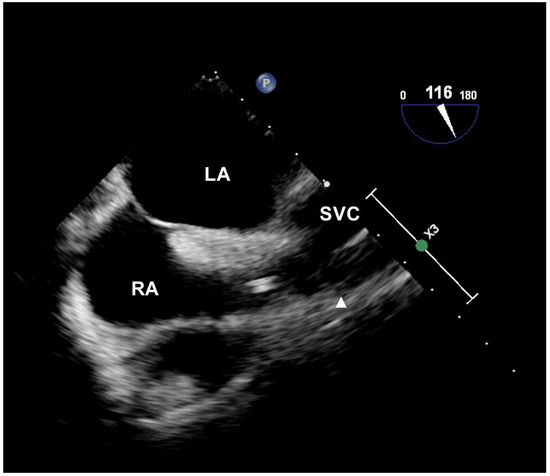

- Ahn, J.H.; Kim, I.S.; Yang, J.H.; Lee, I.G.; Seo, D.H.; Kim, S.P. Transoesophageal echocardiographic evaluation of central venous catheter positioning using Peres’ formula or a radiological landmark-based approach: A prospective randomized single-centre study. Br. J. Anaesth. 2017, 118, 215–222. [Google Scholar] [CrossRef]